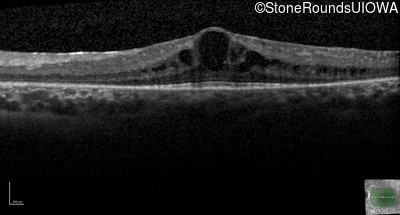

Optical Coherence Tomography - Left - 20/50

Exemplar / OCT Stack

OCT Stack